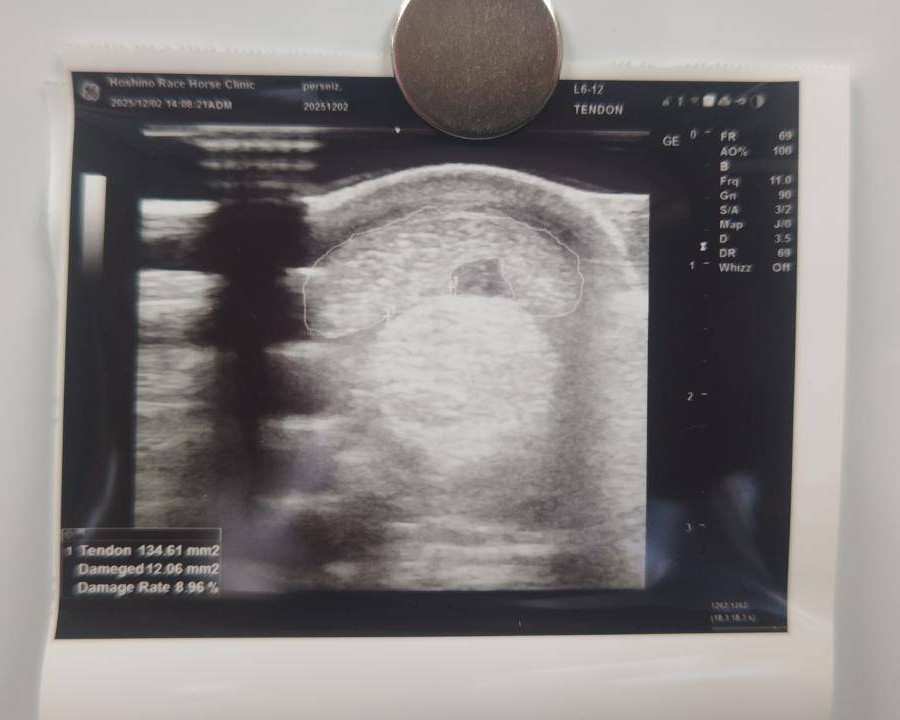

8月8日の川崎1400m戦から復帰し9月24日の浦和1500m戦で2着。前走11月19日の川崎1500m戦では3コーナーから差を詰め3/4馬身差の2着に入るも、次走へ向けた12月2日の調教で右前肢屈腱炎(損傷率9%)の発症が判明。前走の内容が良く馬体重も増えて期待していましたが、頭数整理も都合もあり今回のオークションへ出品いたしました。